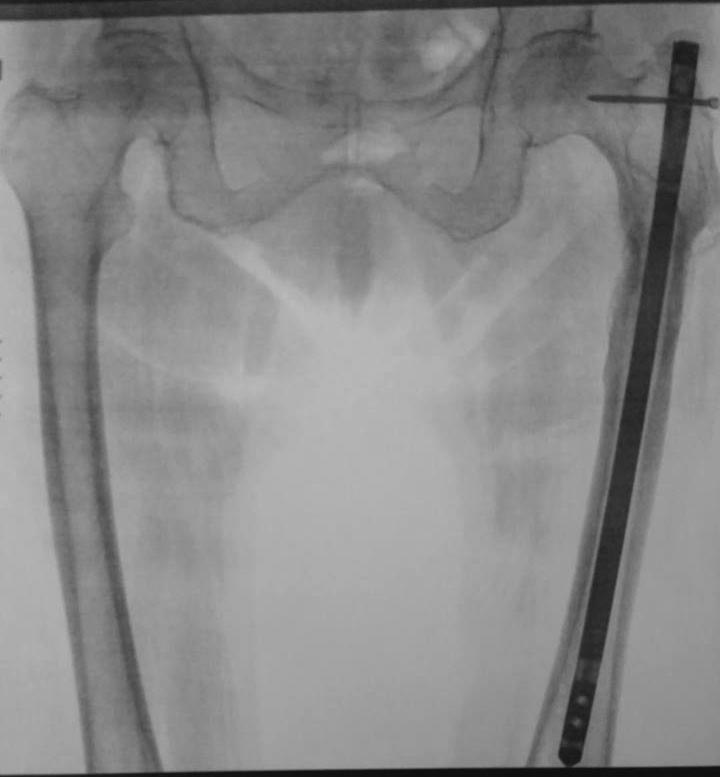

Re: Посттравматическая варусная деформация бедра